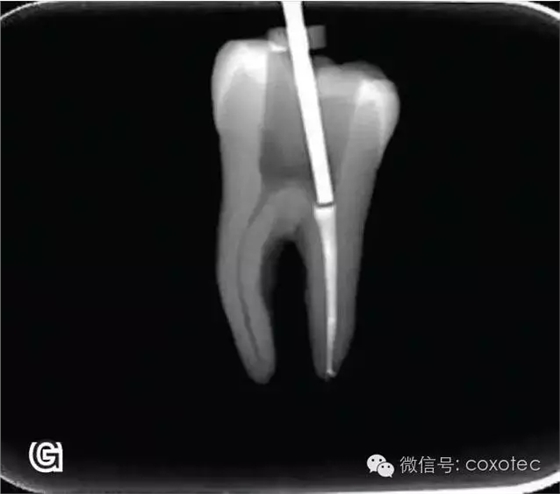

將攜熱器工作尖向根尖加熱加壓至距參照點約2 mm處,關閉加熱器,保持根向壓力,使工作尖前進到參照點處。保持加壓狀態(tài)10秒鐘(圖6)。

圖6 連續(xù)加壓,A、B.攜熱器加壓 開啟加熱器1秒鐘,迅速退出攜熱器工作尖,帶出中上段多余牙膠尖。用小號垂直加壓器向下加壓,完成根尖段的充填(圖7)。

圖7 退出攜熱器工作尖,A.垂直加壓器加壓 B.根尖段的充填完成 在完成根尖段的充填后,使用熱塑牙膠注射儀對根管中上段進行分層充填,一般分2~3次完成充填,每次充填均使用相應直徑大小的垂直加壓器進行加壓。拍片確認充填效果(圖8)。